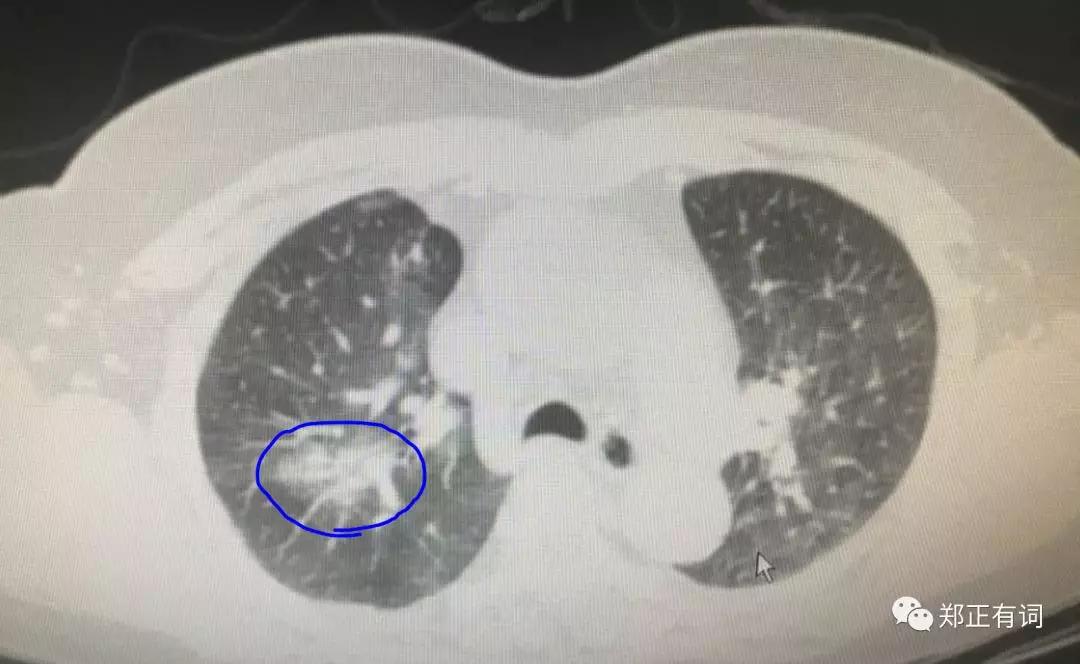

这是一个海南籍的病友,听说广医肿瘤看肺癌不错,就经由熟人介绍过来求诊。入院以后完善CT检查,发现这个病人右上肺近纵隔面存在一个最大径约16mm的实性结节;

而与此同时,右上肺尖段还有一个混合实性结节,疑似恶性。

入院后积极完善相关检查,未见明显转移征象,妥妥的可手术切除适应症。但与此同时,我们又发现了一些问题。